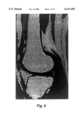

FIGS. 5(a)-5(d) comprise example quadruple field-echo MRI images, showing a human knee, produced in accordance with the present invention;

FIGS. 5(a)-5(b) are examples of MRI images of a human knee obtained using the quadruple field-echo sequence of the present invention with TR=300 ms, for four consecutive echo times (TE) corresponding to: (a) TE=10.3 ms, (b) TE=20.6 ms, (c) TE=30.9 ms and (d) TE=41.2 ms. The average signals of the highlighted ROIs are shown plotted in FIG. 8 which also includes the second scan data having TR=600 ms. The knee images were acquired using an FOV (field of view) of 17.0×17.0 cm2, a data matrix of 128×256 data points, four "slices" at 5 mm thickness, NA=4 and a total acquisition time of 7 min. 41 sec. for the two scans.

FIG. 6 shows an example fat fraction image of a human knee that was obtained by applying the QWFS data processing method of the present invention on a pixel-by-pixel basis to the data used to generate the images depicted in FIGS. 5(a)-5(c).